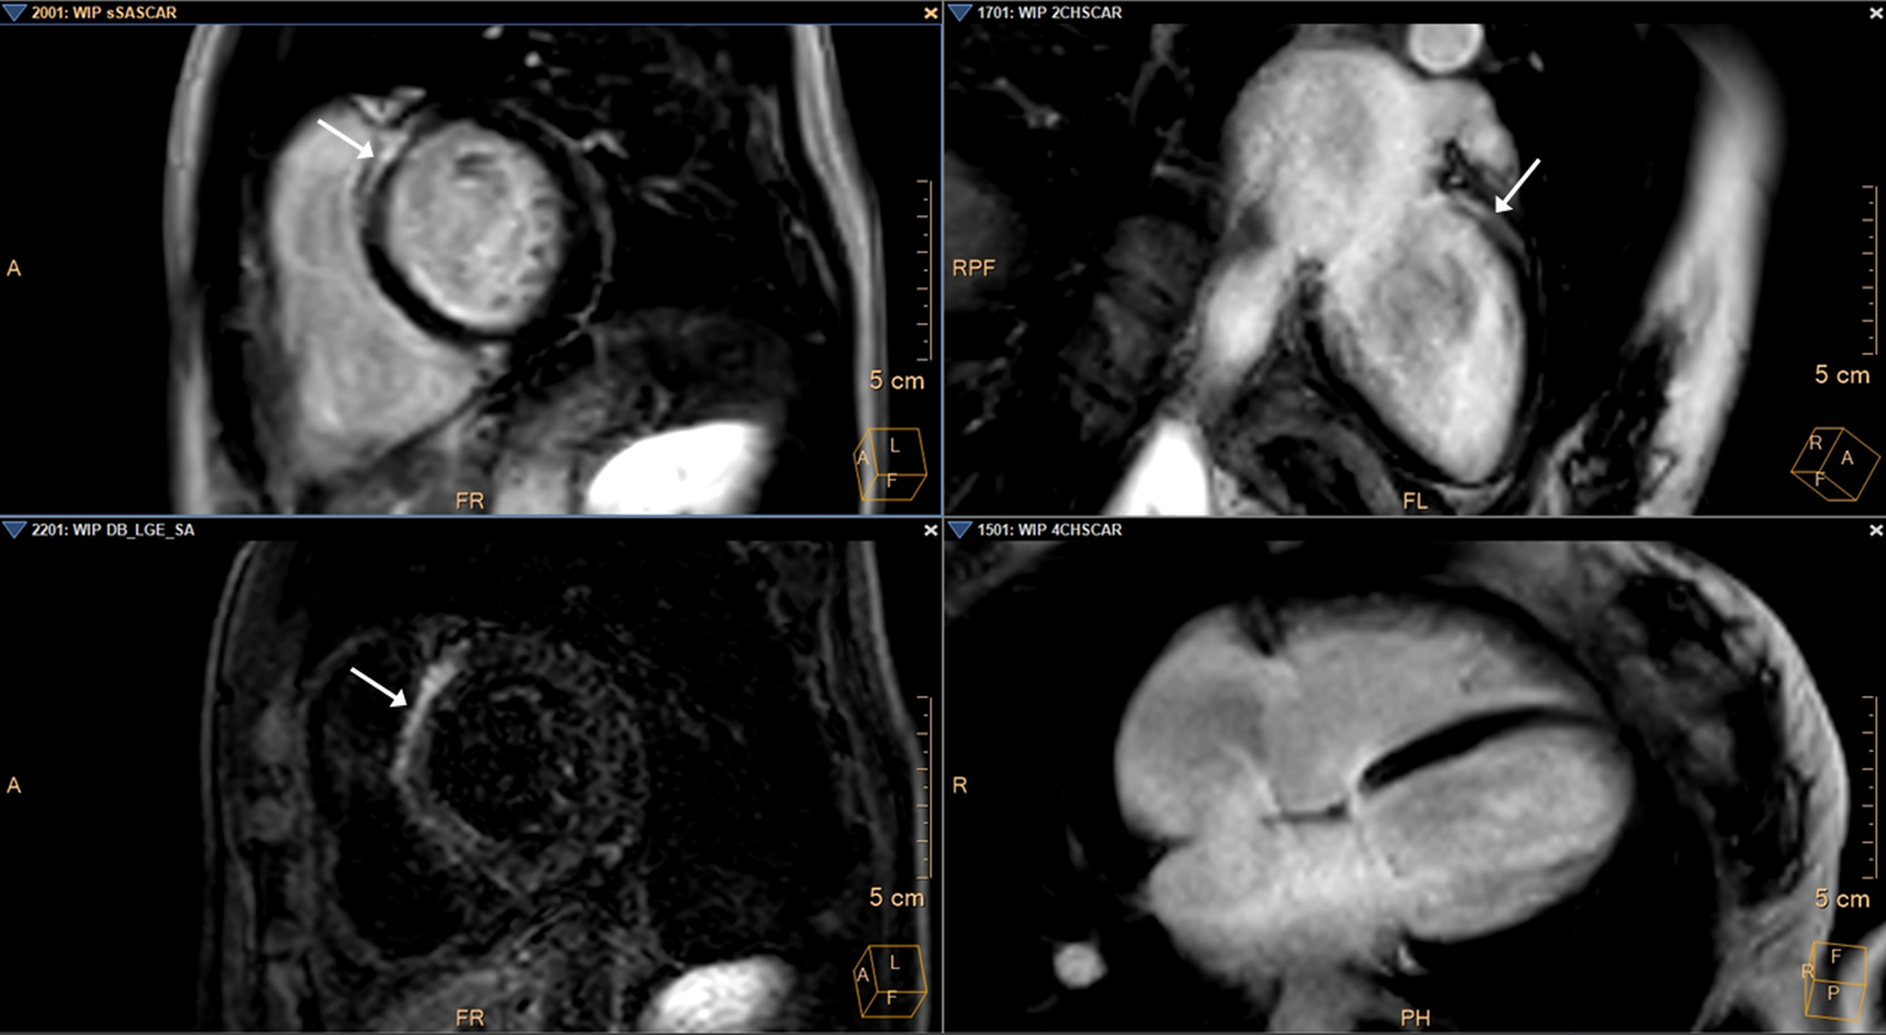

Die CMR (Bild 3) erbrachte den Nachweis eines streifigen, intramyokardialen Fibroseareals des LV anteroseptal (basal)/im Bereich der aorto-mitralen Kontinuität (AMC) aber keinen Nachweis einer myokardialen Infarktnarbe/regionalen Fibrose des RV bei insgesamt normalen Ventrikeldimensionen mit einer interventrikulären Septumdicke von 8mm und normaler Ventrikelfunktion.

Kardiovaskuläres MRT

Bild 3: Kardiovaskuläre MR (CMR): Die Spätaufnahmen nach Kontrastmittelgabe ("Late-Gadolinium Enhancement", LGE) zeigen in der basalen Kurzachsengeometrie (oben links), im 2-Kammerblick (oben rechts) sowie nach zusätzlicher Suppression des Blutsignals in identischer Kurzachsengeometrie (sog. "Darkblood-LGE", unten links) ein intramyokardiales Fibroseareal anteroseptal (basal)/im Bereich der aortomitralen Kontinuität (weiße Pfeile).